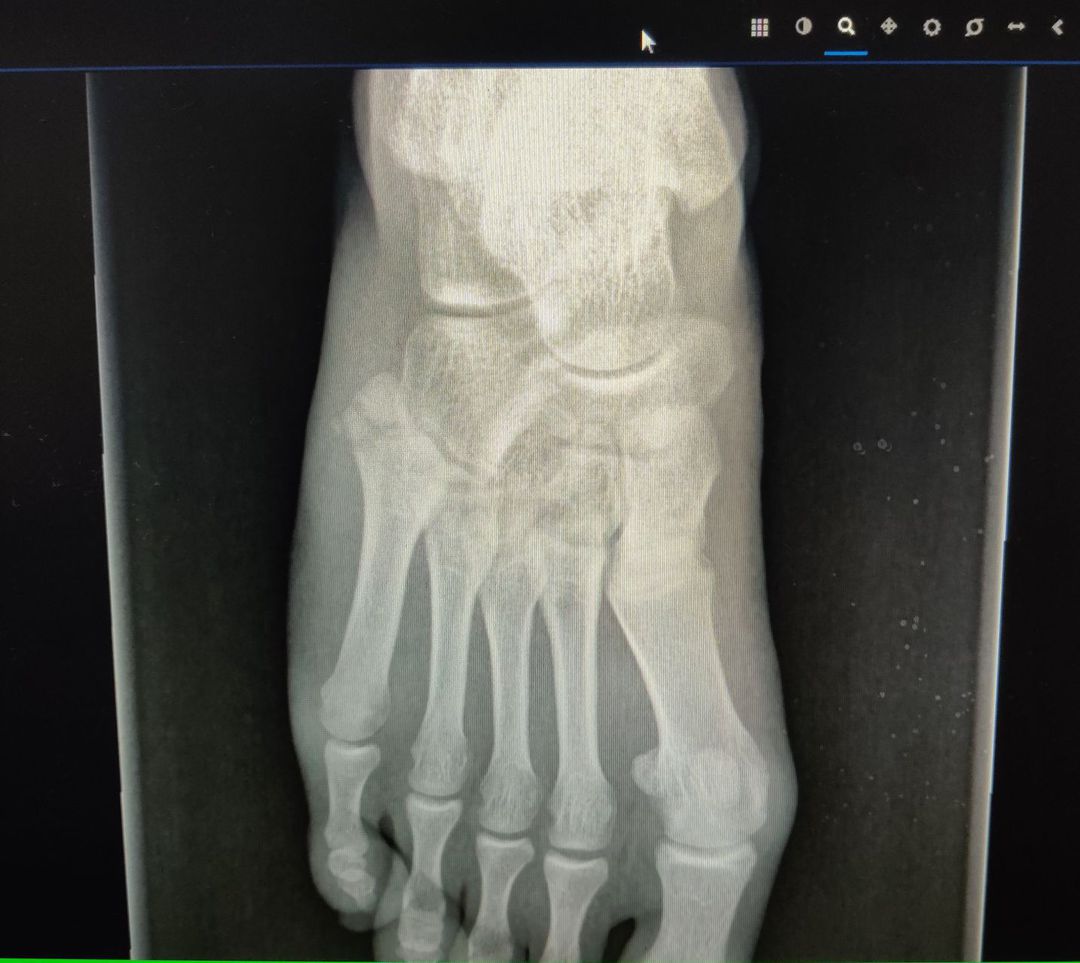

Do you see a fracture?

5th metatarsal

Jones fracture fracture of proximal 5th metatarsals

5th metatarsal fractured

Tip of 5th metatarsals